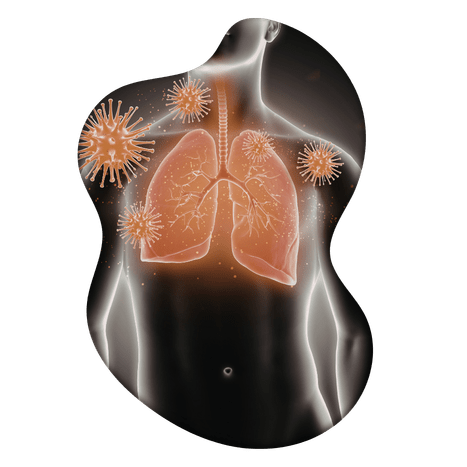

Tuberculosis (TB) is a serious infectious disease that mainly affects the lungs. It is caused by Mycobacterium tuberculosis bacteria and spreads through the air when an infected person coughs or sneezes. This condition can cause symptoms such as persistent cough, chest pain, coughing blood, fatigue, fever, night sweats, and weight loss. Without proper treatment, TB can damage lung tissues and may spread to other parts of the body.

Tuberculosis (TB) is a serious infectious disease in which the lungs (and sometimes other organs) become infected by Mycobacterium tuberculosis. It spreads through the air when an infected person coughs, sneezes, or talks. TB commonly causes symptoms such as persistent cough (sometimes with blood), chest pain, fever, night sweats, fatigue, and weight loss. If not treated properly, it can lead to severe lung damage and complications affecting overall health.

Tuberculosis (TB) is a contagious infectious disease caused by the bacterium Mycobacterium tuberculosis. It primarily spreads through the air when an infected person coughs, sneezes, speaks, or laughs, releasing tiny droplets containing the bacteria. When another person inhales these droplets, the infection can enter the lungs and begin to develop.

From a modern medical perspective, TB infection occurs more easily in individuals with weakened immune systems. Factors such as malnutrition, poor living conditions, overcrowding, and lack of proper ventilation significantly increase the risk of transmission. People with conditions like diabetes, HIV, or those undergoing long-term medication may also be more vulnerable.

Tuberculosis (TB) can develop gradually after infection with Mycobacterium tuberculosis, primarily affecting the lungs. It spreads through airborne droplets when an infected person coughs or sneezes. In many cases, symptoms appear slowly and may worsen over time if not treated. Early diagnosis and proper medical treatment are essential to prevent complications and ensure recovery. Along with standard treatment, supportive care helps strengthen immunity and improve overall health.